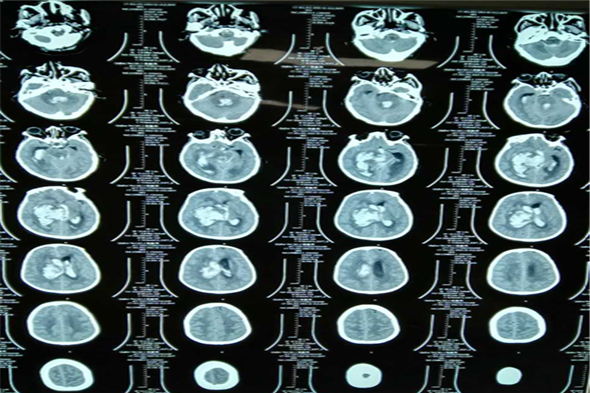

神经外二科近期收治3名大量脑出血的病人,其中2名患者已经出现了脑疝,生命垂危,入院后吴卫东主任果断决定行急诊微创手术治疗,行一侧钻孔血肿清除引流术加一侧脑术外引流术。术后病人恢复较好,一侧散大瞳孔回复,生命体征平稳,现已进入康复治疗阶段。以下为3名患者术前术后CT检查结果。

病例一 李某,男,35岁,脑出血、脑疝。

病例二 孙某,女,63岁,脑出血、脑疝。

病例三 王某,男,66岁,脑出血、脑疝。